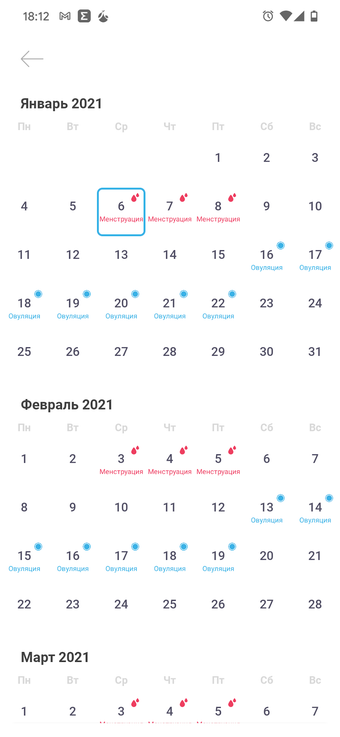

L'applicazione "Gravidanza" è una guida completa per le donne in gravidanza. Contiene molte informazioni sulla gravidanza, sia fisiche che emotive. La guida ti aiuterà durante il tuo percorso di gravidanza dal momento del concepimento fino alla nascita del bambino. Sarai in grado di vedere cosa sta succedendo al tuo corpo e al tuo bambino ogni settimana, oltre a imparare cosa fare e cosa non fare per avere un bambino sano.

Questa applicazione non è solo una guida per le donne in gravidanza, ma anche un forum dove puoi discutere i tuoi problemi di gravidanza con altre donne in gravidanza. Puoi far loro domande e ottenere i loro consigli. Inoltre, l'applicazione contiene vari test, come un test per determinare il sesso del bambino e la data di nascita.